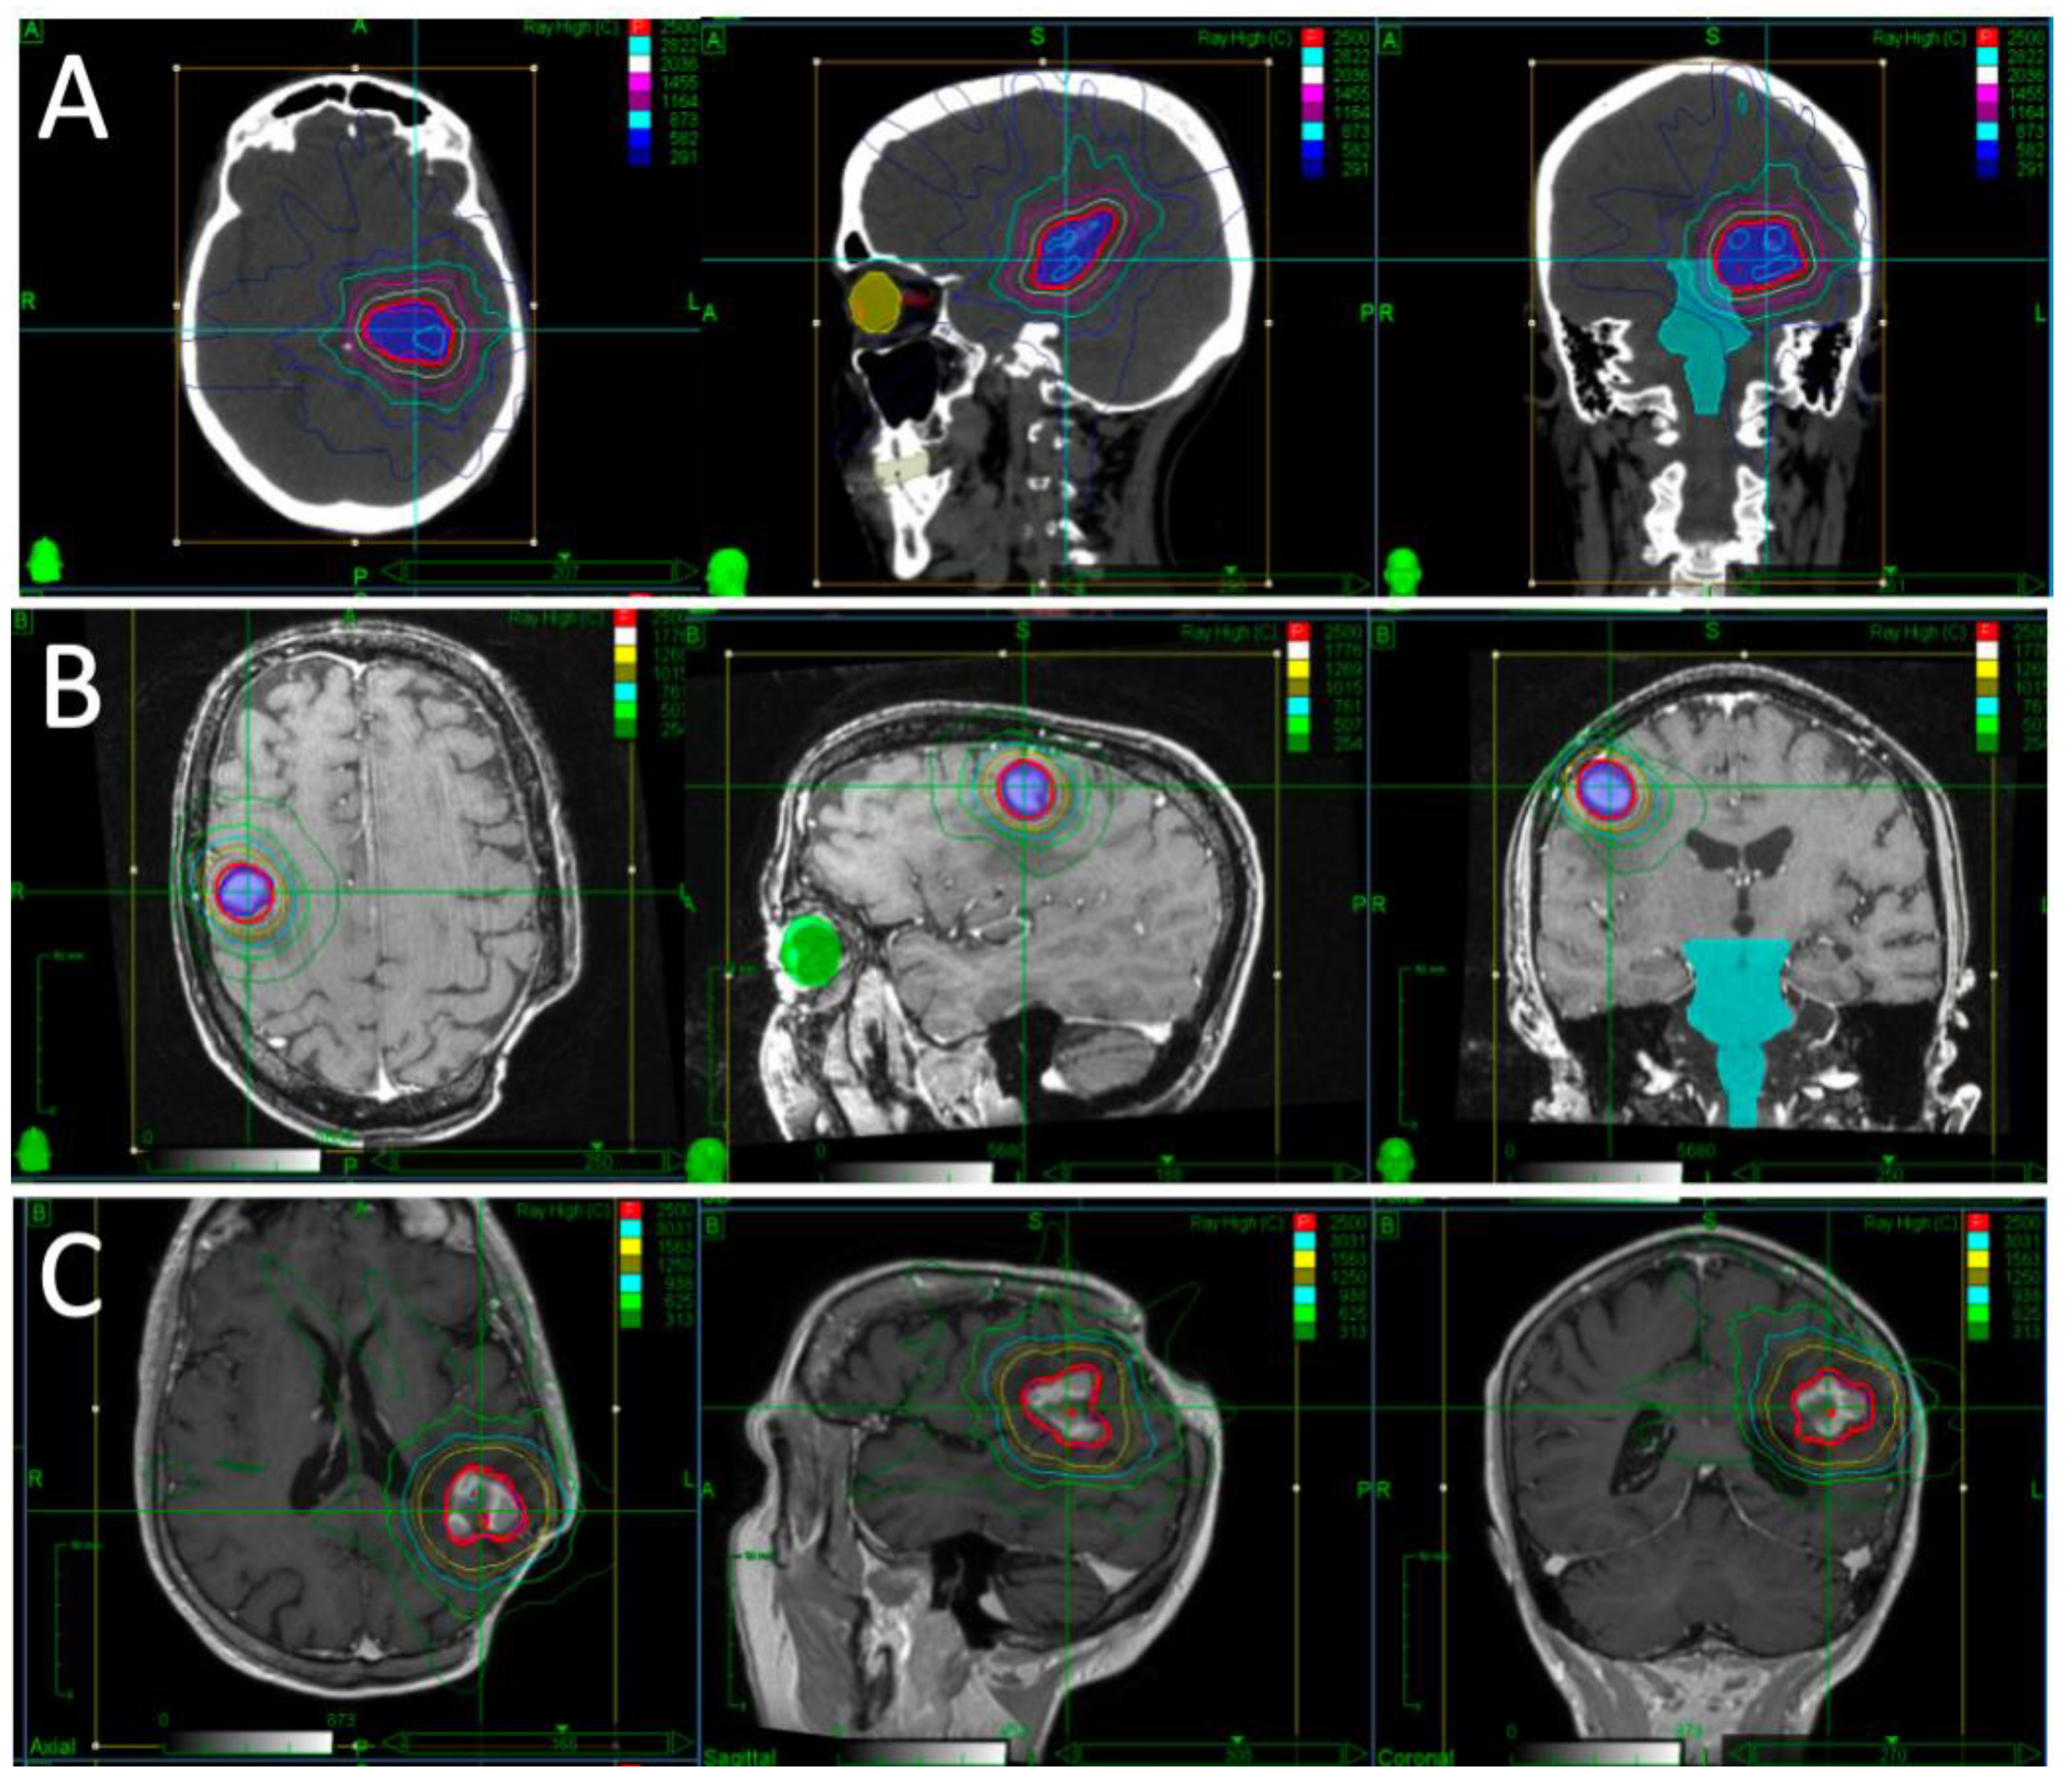

A patient presented with falls, short-term memory loss and word-finding difficulties. An MRI revealed a 4.6 × 4.2 × 4.0 cm mass centered in the left thalamus. Due to the rapid progression of symptoms and development of hemiplegia, they underwent partial resection. Pathology revealed diffuse large B-cell lymphoma (DLBCL). They proceeded to receive two cycles of high-dose methotrexate and cytarabine but had progression while on chemotherapy, with MRI demonstrating a 1.8 × 1.2 cm enhancing lesion in the left middle cerebral peduncle and thalamus. Their KPS was 30–40. After multidisciplinary discussion, it was decided to proceed with fSRS to this lesion. Representative images of their fSRS are shown in Figure 1. fSRS was completed 3 months after their partial resection and 2 months after their last chemotherapy. They had a complete radiologic remission and regained much of their neurologic function, with some residual fatigue and right-sided weakness and sensory deficits.

Figure 1. Target volumes and dose distribution for Case 1, outlining their first (A), second (B), and third (C) courses of fSRS. Repeat fSRS was necessary due to regional recurrences, but no in-field recurrences were noted in their case. The red isodose line represents the prescription dose of 25Gy.